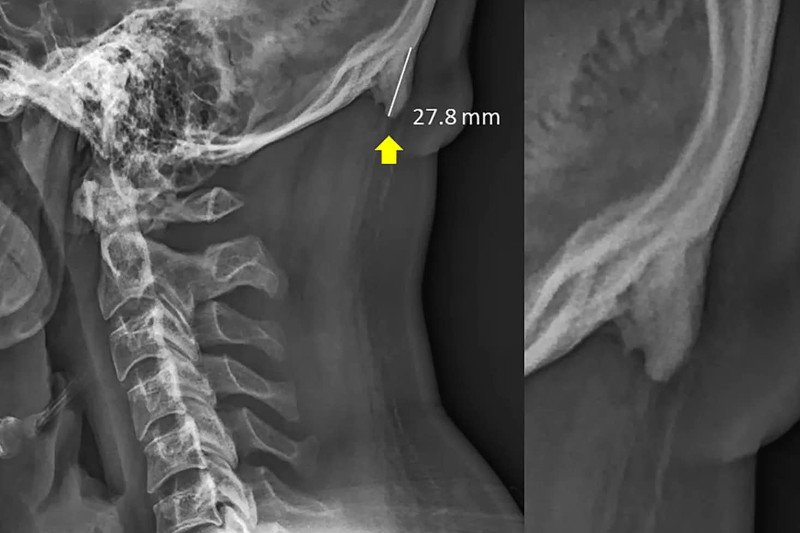

Australijskie badania biomechaniczne, które rozpoczęto 3 lata temu, wskazują, że telefony wpływają nie tylko na nasze zachowanie, ale i prawdopodobnie powodują zmiany w ciele. To może zabrzmieć absurdalnie, ale naukowcy podzielili się zdjęciami rentgenowskimi czaszek młodych ludzi, w których zaobserwować można coś na kształt kolców czy rogów.

Pojawiają się one z tyłu, tuż nad szyją i powstają na skutek przechylenia głowy do przodu, ponieważ ciężar z kręgosłupa przekłada się na mięśnie z tyłu głowy. Można to porównać do pogrubiania się skóry w miejscu nacisku czy otarcia.

Pierwszy artykuł badaczy na ten temat został opublikowany w Journal of Anatomy w 2016 roku. Dotyczył 218 zdjęć rentgenowskich osób w wieku od 18 do 30 lat i sugerował, że rozrost kości można zaobserwować u 41 proc. młodych dorosłych, częściej u mężczyzn niż kobiet.